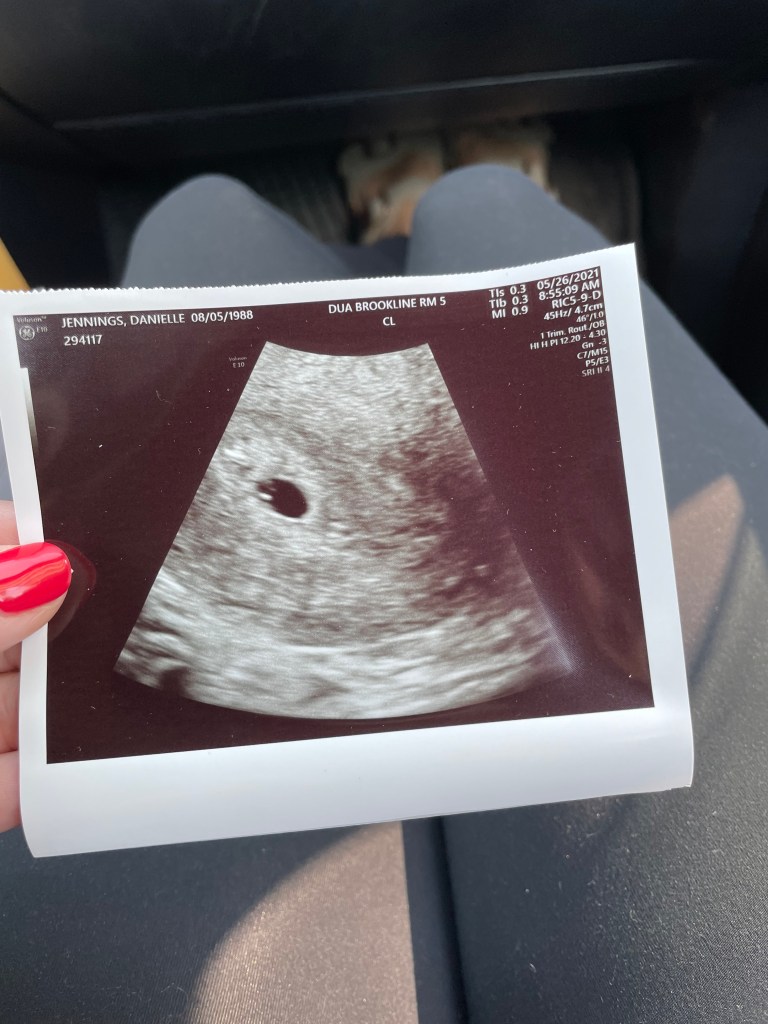

5/26/2021- I don’t think Dave and I spoke the whole drive to Brookline, we were feeling every emotion. We were put in the room right away and the exam began. It was good news, the gestational sac was right where it needed to be. Ectopic off the table. With one relief comes the next fear, we are only 5 weeks at this point so it was still way too early to know if the pregnancy is viable. A heartbeat is usually not detected until 6/7 weeks. One victory today but more waiting, 6/2 would be our next sono.